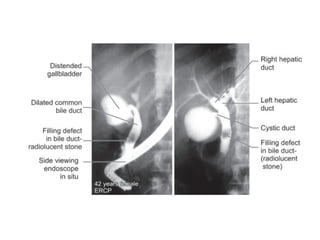

 ERCP to visualise the site of obstruction,

brush biopsy, bile sample for analysis.

Choledocholithiasis

Primary bile duct stones

 Stones that form in bile duct itself.

Clinical features

 Charcot's triad

„

 Obstructive jaundice: Itching, clay

colored stool „

 Associated pancreatitis may cause pain

in the back „

 Abdominal tenderness may be present

in right upper quadrant during an

attack of cholangitis „